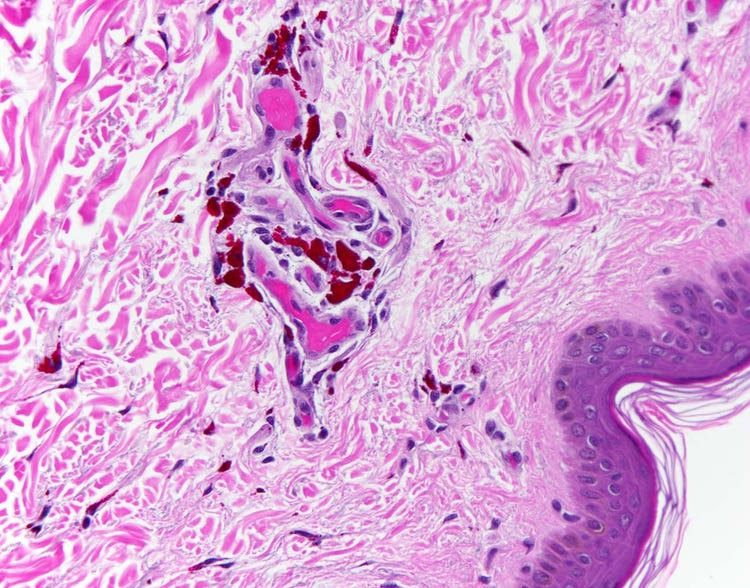

Tattoo red pigment shown under the microscope

Section of human skin bearing a tattoo. Individual pigment granules are visible in the dermis, the deep layer of the skin, under high magnification. Other pigment granule colors that are identifiable under the microscope are black, blue, and gold. Captured on an Olympus BX43 microscope with a DP26 camera. Image courtesy of Marianne Hamel.